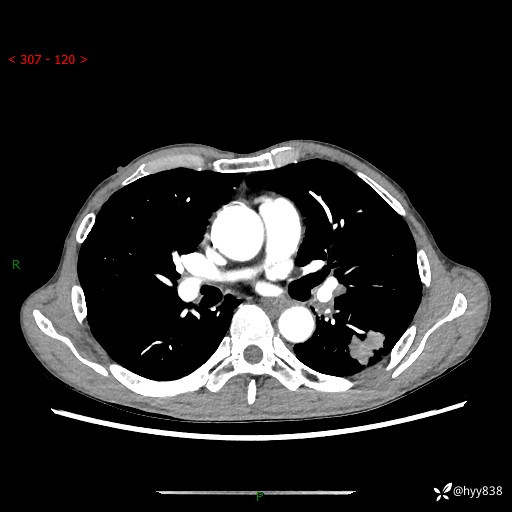

现病史:患者于1月余前无明显诱因出现背部疼痛不适,无明显咳嗽、咳痰、胸闷、咯血、发热等不适,后于2024.5.3至当地市人民医院行胸部CT示:左肺下叶结块,大小约2.2cm*2.6cm,双肺多发小结节,双肺感染性病变,部分纤维增值灶,慢支并双肺局限性肺气肿,肺大泡,纵隔淋巴结增大并部分钙化,冠脉区及大血管壁钙化,双侧胸膜局限性增厚;后口服莫西沙星2周。2024.6.12复查胸部CT示:左肺下叶结块影形态较前饱满,较大截面范围约2.8cm*2.3cm,边缘可见细短毛刺及分叶,性质待查。现患者为求进一步诊治来我院,门诊以“肺占位”收入我科。 起病来,患者精神、食欲、睡眠尚可,大小便正常,体力体重轻微下降。

胸部CT平扫+增强

各期CT值:48hu 100hu 78hu